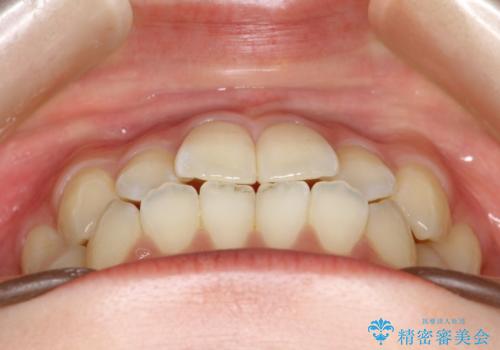

前歯のガタつき、下顎の前突感を治したい インビザライン矯正例

- 学生時代に矯正治療を経験されていましたが、その後の後戻りによる前歯の叢生・下顎の前突感を主訴に来院されました。叢生や口元の突出感が軽度であった為、非抜歯にて側方拡大やIPRを組み込んでインビザラインにて治療を計画しました。前歯部にクロスバイトがあり、治療途中に上顎前歯が下顎前歯を乗り越えなければならない時期もありましたが、患者様の協力的なマウスピース装着もあり、良好な配列を達成しました。上下左右の親知らずは、当院にて矯正開始前に抜歯しました。